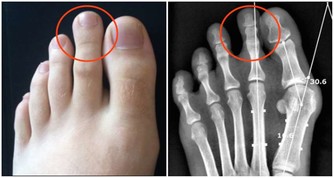

水腫

飲水太多,或者是睡眠時間過長、過於肥胖等,眼瞼、臉部、小腿等部位可以出現輕微的水腫,或者一過性的水腫。但如果不是這些原因引起的水腫,就要懷疑是不是腎臟出了問題。